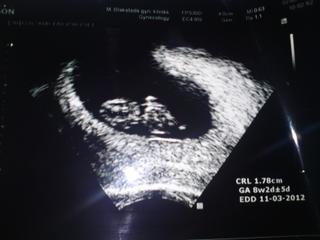

Ahojte babule...tak ja som doma ad lekarky.......mame 1,78 cm a srdiecko...... 😀 😀 😀

Aj som ho videla a aj pocula......som taka stastna....konecne. 😀

Prikladam dokaz....🙂

@zuzanka7117 jeeej krasne babatko :o))) drzkam palce neto takto dalej pokracuje.a pozeram ze ti zmenili datum porodu na 11.3

@micikatka ano zmenili.....ale k ked si to pocitam s 30 dnovym cyklom, vychadza to na 13.......aj tak tam pise, ze 8+2dni+-5dni....takze ktovie....ona to ratala podla koliecka a asi podla 28 dnoveho cyklu...ale to je jedno, hlavne ze je.... 😀